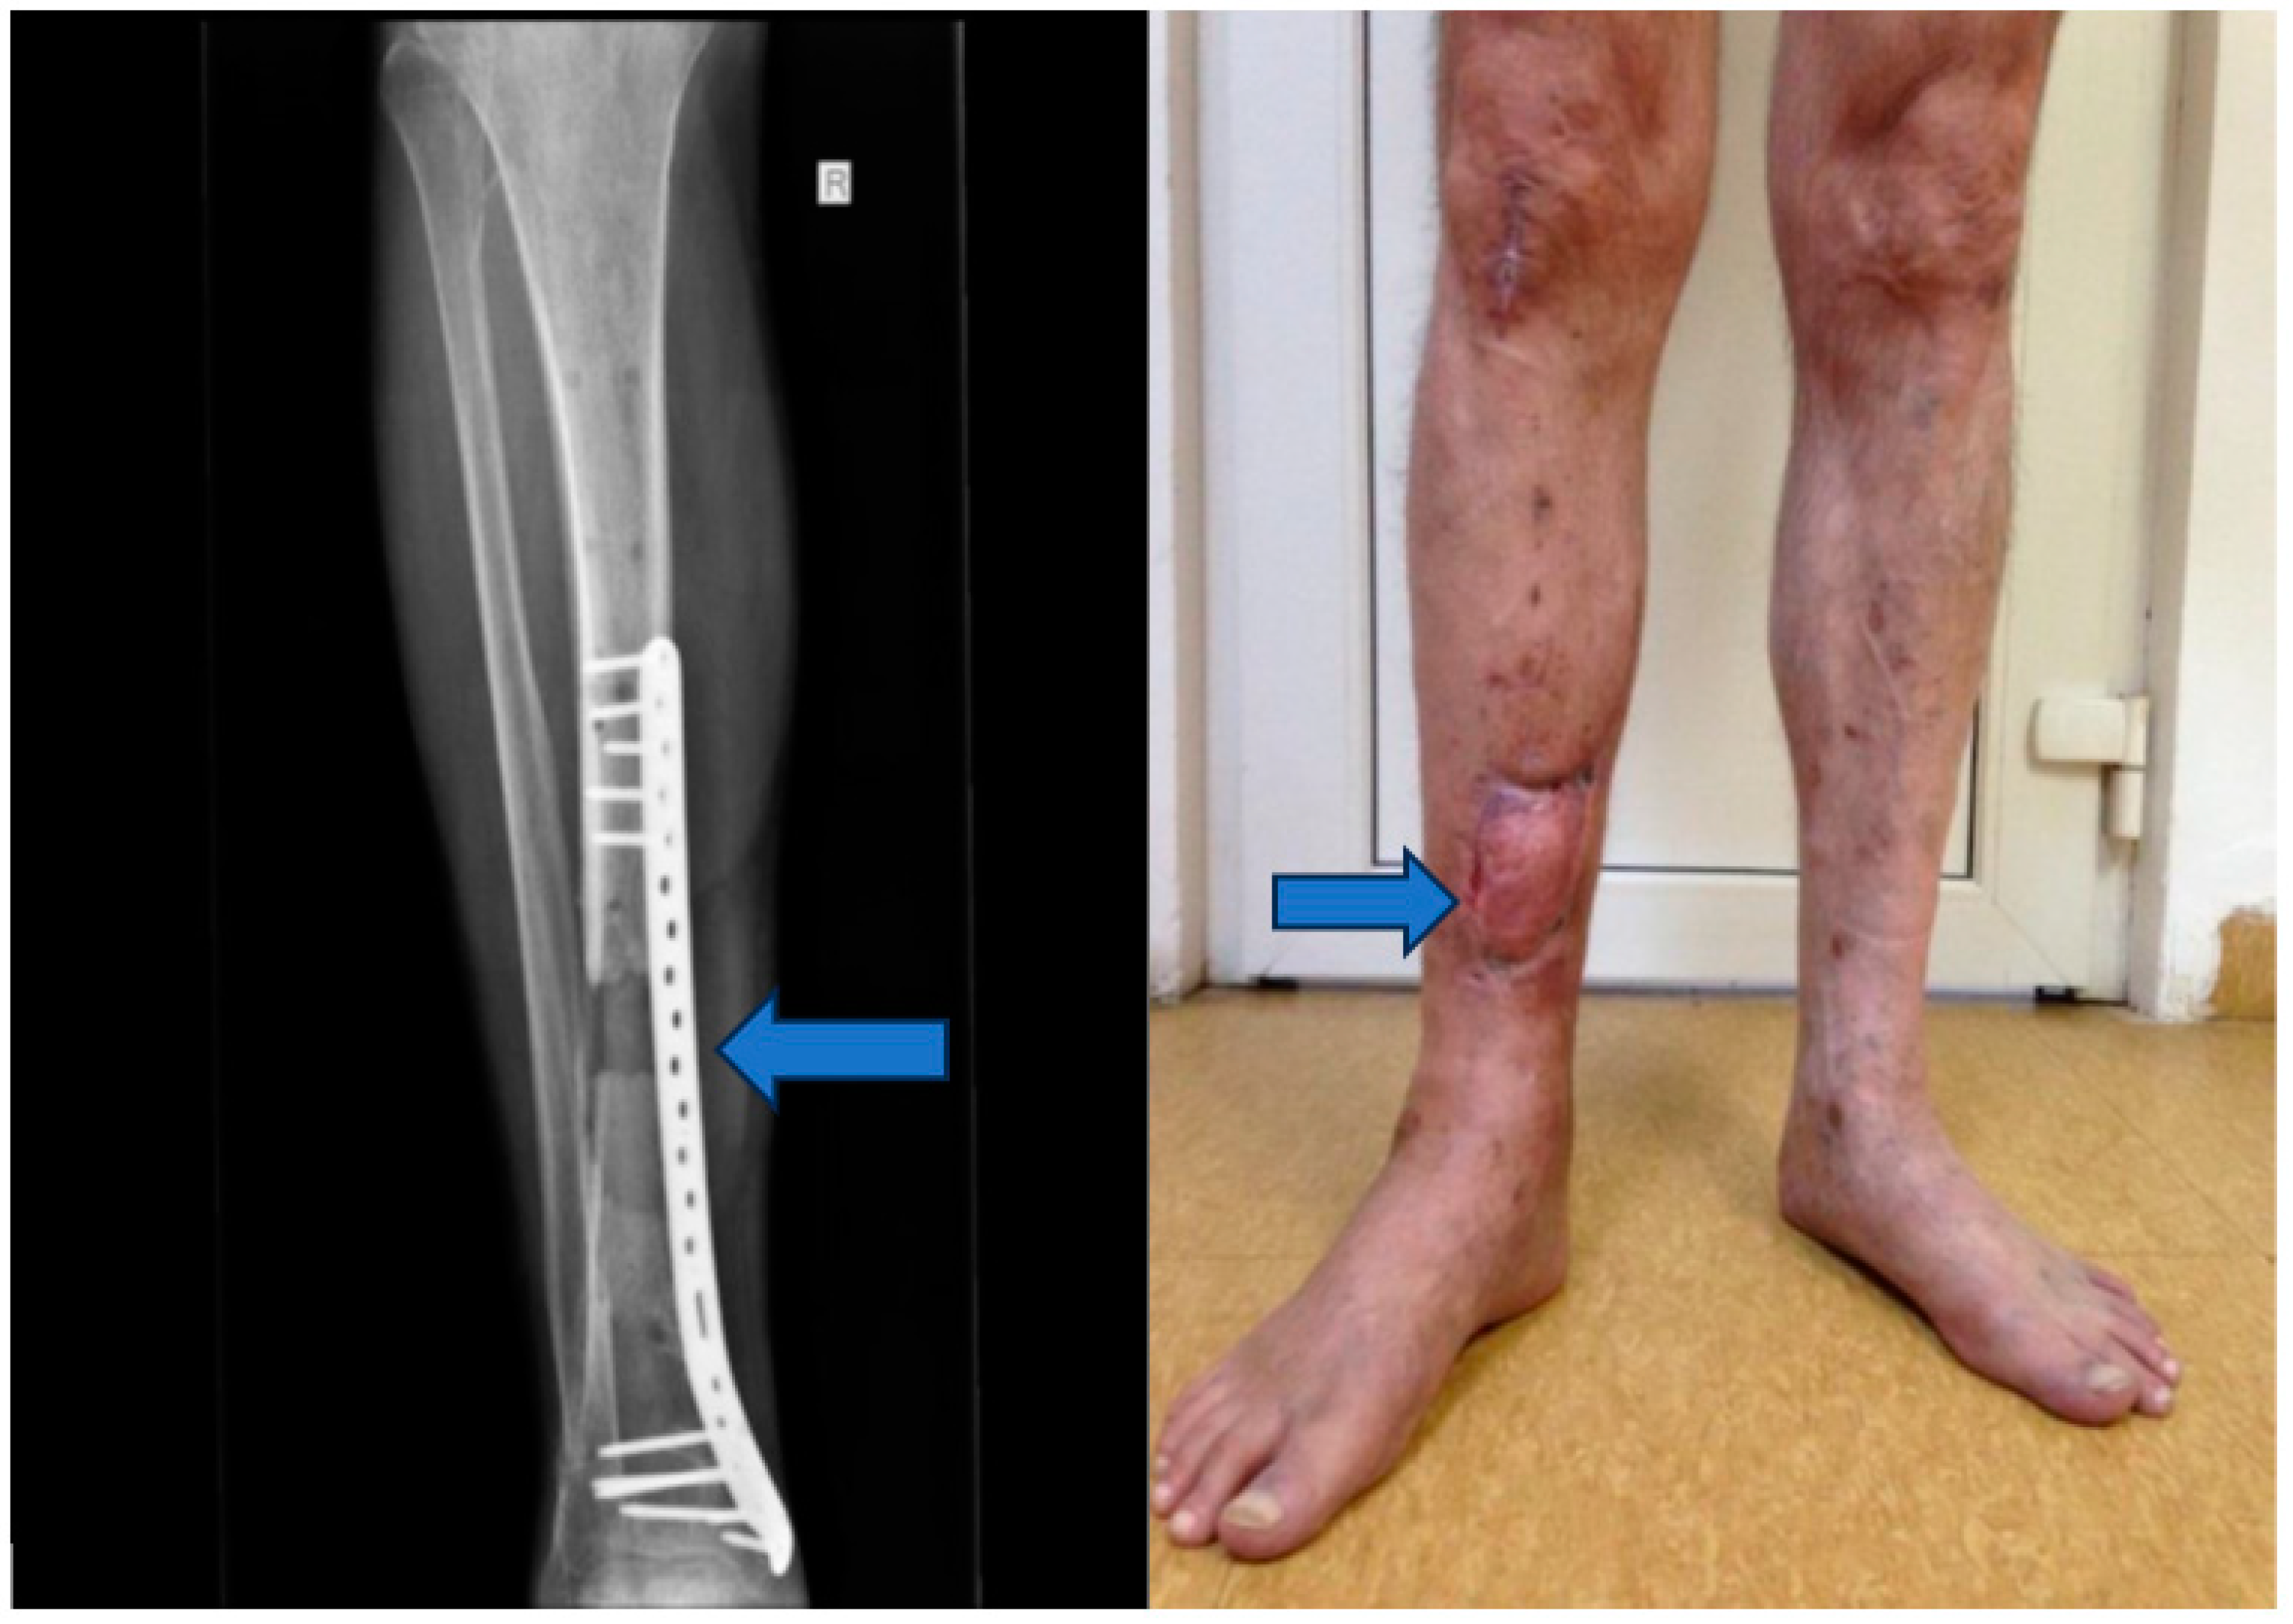

Stage 1: initial stabilization and osteosynthesis (Figure 1).

Objective: To provide immediate stabilization of the open tibial fracture and initiate the process of bone fixation.

Methods: The patient underwent external fixation in the emergency room.

Figure 1. (A,B) External fixation in the emergency room.

Figure 6. Musculocutaneous flap and internal fixation was achieved using a blocked Less Invasive Stabilization System (LISS) plate.

Stage 4: Flap integration and internal fixation (Figure 6).

Objective: To ensure the integration of the musculocutaneous flap and provide internal fixation to stabilize the tibia.

Methods: After an 8-week integration period, the musculocutaneous flap was deemed stable. The external fixator was removed, and internal fixation was achieved using a blocked Less Invasive Stabilization System (LISS) plate, which was inserted utilizing the Minimally Invasive Plate Osteosynthesis (MIPO) technique.